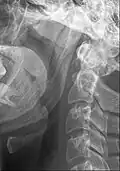

Ligamento estilo-hióideo ossificado ou processo estiloide alongado

O ligamento estilo-hióideo normalmente contém uma pequena cartilagem no seu centro, que costuma ser parcialmente ossificada na síndrome de Eagle .[3]